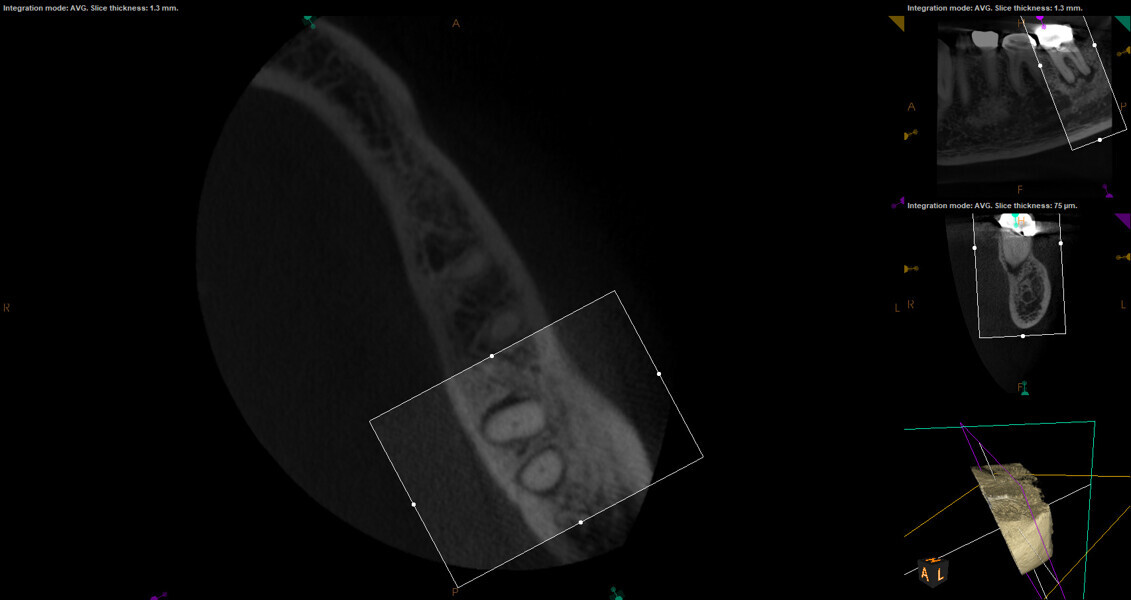

Fig. 17a: Case assisted with CBCT to determine anatomy pre-operatively. Note the multiple cross sections moving apically and the correlation to the 2-D view. Note also the conservative taper in relation to the root width. (Courtesy of Dr. Brett Gilbert)

Fig. 17b: Case assisted with CBCT to determine anatomy pre-operatively. Note the multiple cross sections moving apically and the correlation to the 2-D view. Note also the conservative taper in relation to the root width. (Courtesy of Dr. Brett Gilbert)

Fig. 17c: Case assisted with CBCT to determine anatomy pre-operatively. Note the multiple cross sections moving apically and the correlation to the 2-D view. Note also the conservative taper in relation to the root width. (Courtesy of Dr. Brett Gilbert)

Fig. 17d: Case assisted with CBCT to determine anatomy pre-operatively. Note the multiple cross sections moving apically and the correlation to the 2-D view. Note also the conservative taper in relation to the root width. (Courtesy of Dr. Brett Gilbert)

Fig. 17e: Case assisted with CBCT to determine anatomy pre-operatively. Note the multiple cross sections moving apically and the correlation to the 2-D view. Note also the conservative taper in relation to the root width. (Courtesy of Dr. Brett Gilbert)

Fig. 17f: Case assisted with CBCT to determine anatomy pre-operatively. Note the multiple cross sections moving apically and the correlation to the 2-D view. Note also the conservative taper in relation to the root width. (Courtesy of Dr. Brett Gilbert)